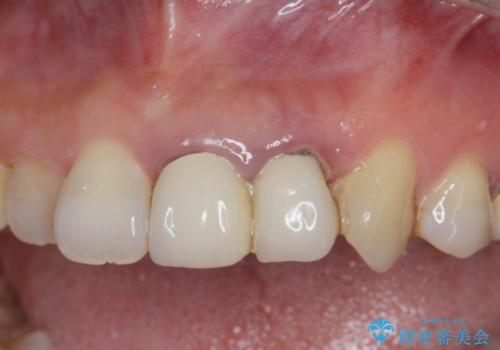

ぐらぐらする前歯 前歯のブリッジ治療

- 前歯がクラグラして噛めないことの改善を求めて来院されました。

X線撮影や歯周組織検査から、クラウン下の虫歯の再発や歯の破折が疑われる状況でした。

精度、周囲の歯の色調にこだわったオールセラミックブリッジを作製し、しっかりと機能・審美性を改善することができました。